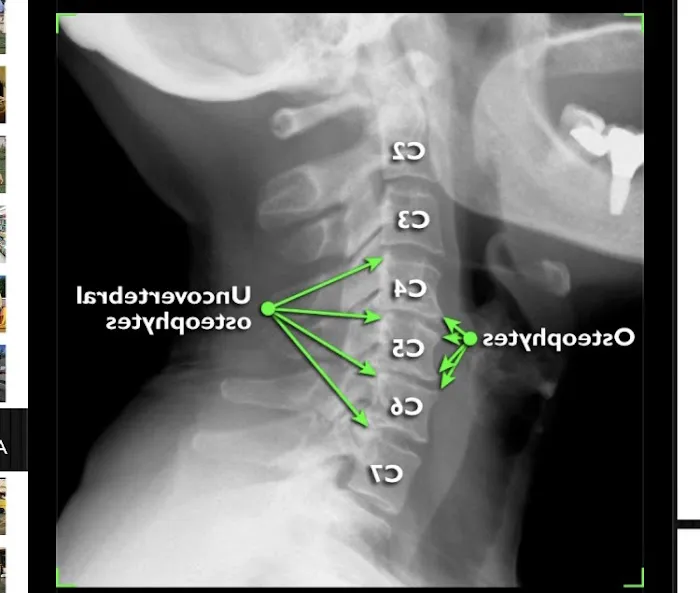

Chiropractic care is a natural healthcare discipline that focuses on the diagnosis, treatment, and prevention of musculoskeletal disorders, with a primary emphasis on the spine and its intricate relationship with the nervous system. The fundamental principle of chiropractic is rooted in the body's remarkable innate ability to heal itself, provided there is no interference with the nervous system's vital communication pathways. Misalignments in the spine, often called 'subluxations,' can disrupt these pathways, leading to pain, muscle dysfunction, and a variety of other health issues. At Carlucci Chiropractic, under the expert guidance of Dr. Kim, the approach is precisely to identify and gently correct these subluxations through specialized chiropractic adjustments. This process aims to restore proper nerve flow, alleviate discomfort, improve mobility, and empower the body to function at its optimal level. For many New Jerseyans, Carlucci Chiropractic offers a vital alternative or complement to conventional medicine, focusing on root-cause solutions for pain and health challenges.

- X-ray